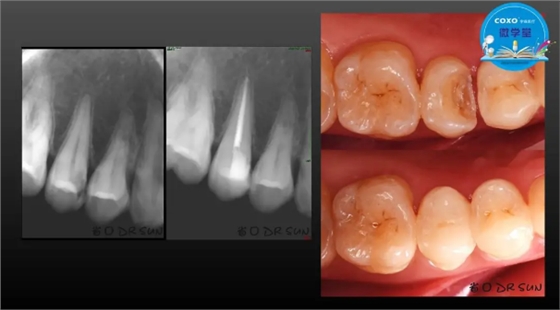

主讲:孙书昱

主任医师,牙体牙髓副主任, 广东省口腔医院牙体牙髓科 主任医师。2003年硕士研究生毕业,研究方向为牙体牙髓病学,擅长于牙体牙髓病的诊断、龋齿、牙髓炎、根尖周病的治疗以及前牙美容修复。